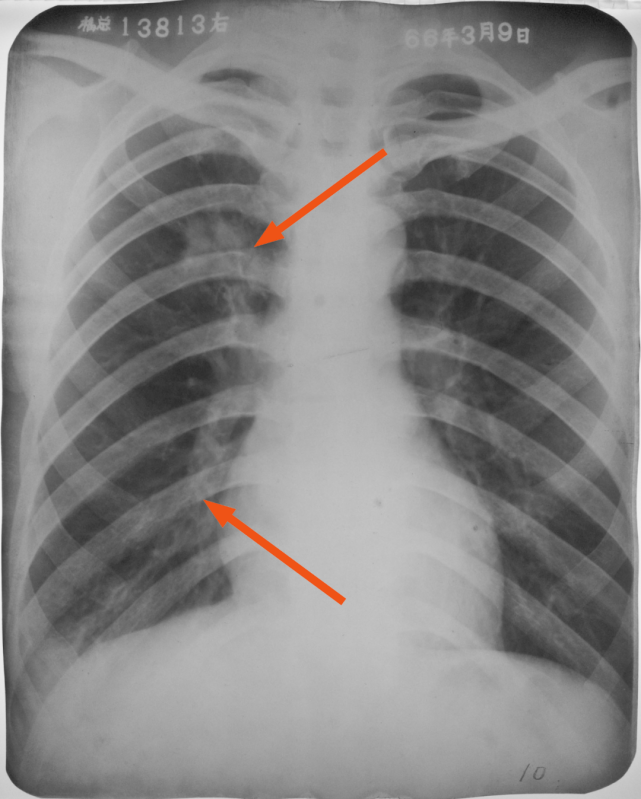

右肺下叶后基底段大叶性炎症

图片

胸部正侧位片:右肺下叶见片状致密影,右侧膈面及邻近胸廓边缘模糊(箭头所示),心缘清楚